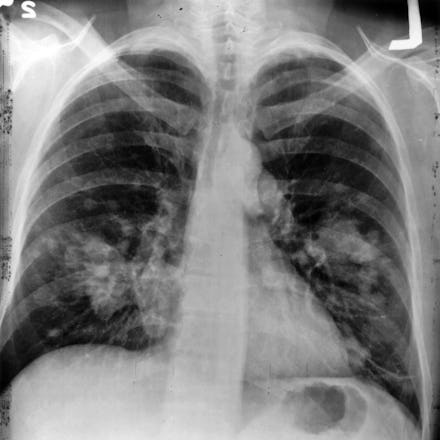

CT scans, on the other hand, can cost about $800 and expose patients to radiation. The cost is the most important part: With such an expensive test, not everyone can afford a CT scan to detect lung cancer.